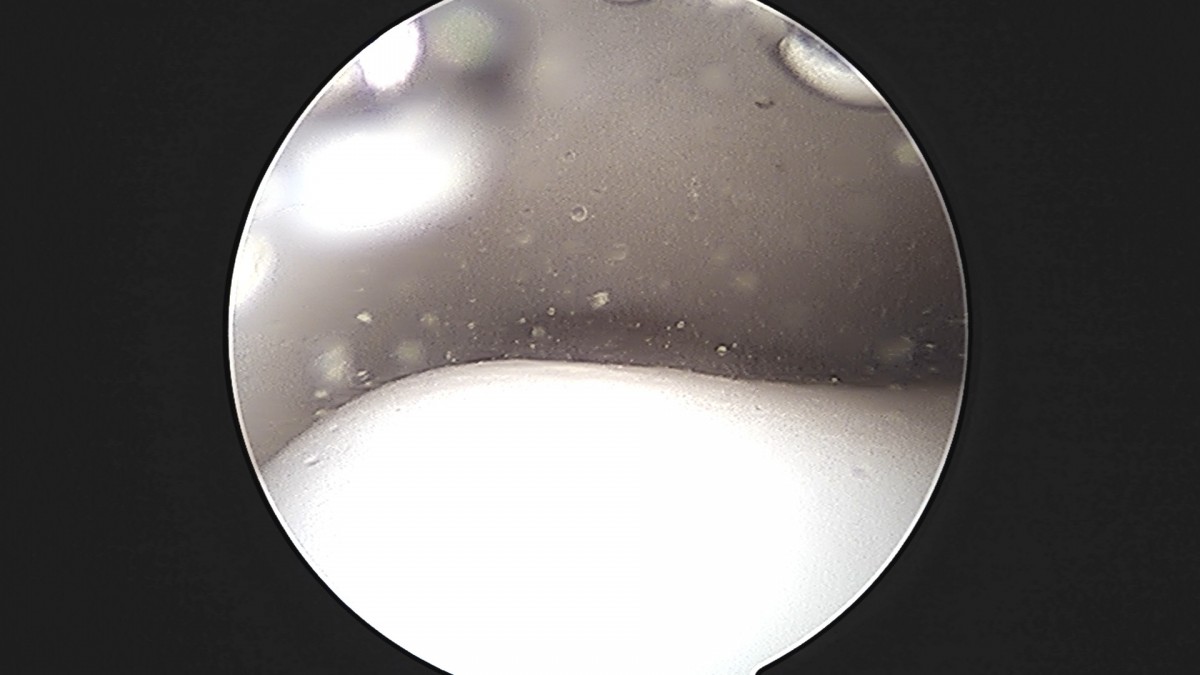

정지영원장님 발목 인대 봉합술 채이O 환자

작성자 최고관리자 댓글 0건 조회 718회 작성일 25-09-16 17:02